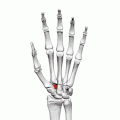

Left hand anterior view (palmar view). Trapezoid bone shown in red.

The left trapezoid bone.